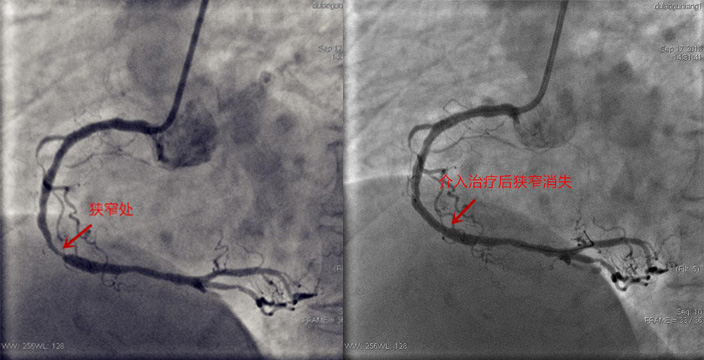

据了解,心脏介入手术是一种新型诊断与治疗心血管疾病技术,经过穿刺体表血管,在数字减影的连续投照下,送入特制的心脏导管,通过心脏导管操作技术对心脏病进行确诊和治疗的诊治方法,它是目前较为先进的心脏病诊治方法,介于内科治疗与外科手术治疗之间,是一种微创的诊治方法。心脏介入相对于外科手术具有多种优势,患者容易接受、损伤小、恢复快,几乎是无痛苦的,“首先这是微创手术,患者创伤小,术后不用卧床,减少痛苦;不用全麻醉,减少麻醉,手术并发症大大减少;费用也较心脏外科搭桥手术相应降低。”王胜文主任说。

“心脏介入的开展,对于长春北部的心肌梗死等心脏病患者是一件好事,患者突发心脏疾病可直接入中医院进行抢救,大大节省了时间。”王胜文主任说,将来要充分利用医疗互联网技术和胸痛绿色通道建设,使患者信息网络实时传递,实现院前急救和院内抢救、各级中医医疗机构转诊及转运网络一体化无缝衔接,开通绿色通道,快速检验、快速报告,诊断明确患者直达介入导管室或重症监护室等措施,降低D-to-B平均时间,挽救病人心肌细胞,改善病人预后,为急性心肌梗死患者搭建起了一条高效通畅的急救“高速路”。